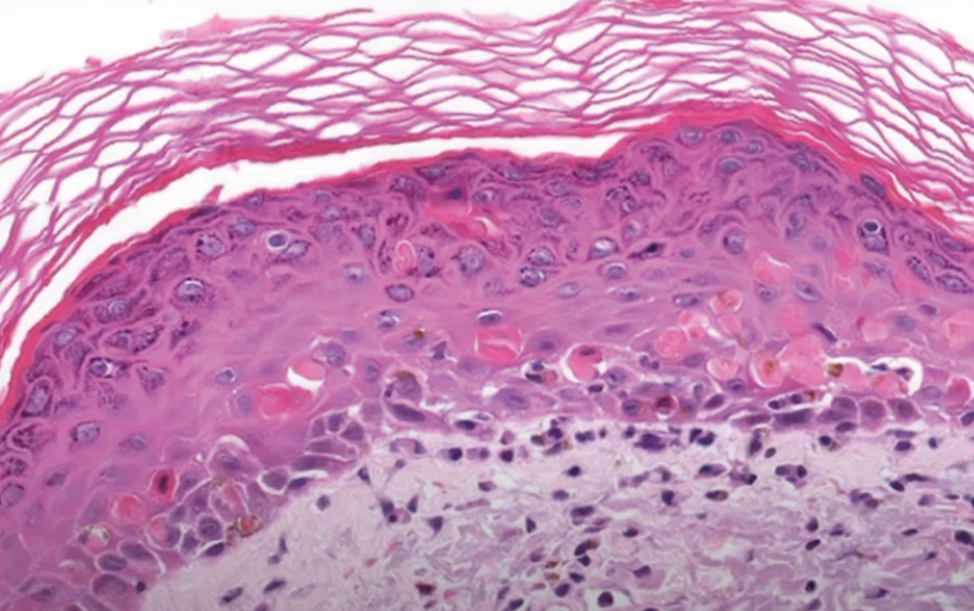

Conclusion of the histologic study (Fig. 2): The mucosal fragment showed hyperplastic multilayered squamous epithelium with acanthosis, parakeratosis, and hyperkeratosis, with pronounced lymphoplasmocytic infiltration of the stroma and a band-like lymphoid infiltrate.

Fig. 2. Histological findings (haematoxylin and eosin staining, ×200).

Рис. 2. Гистологическая картина (окрашивание гематоксилином и эозином, ×200).